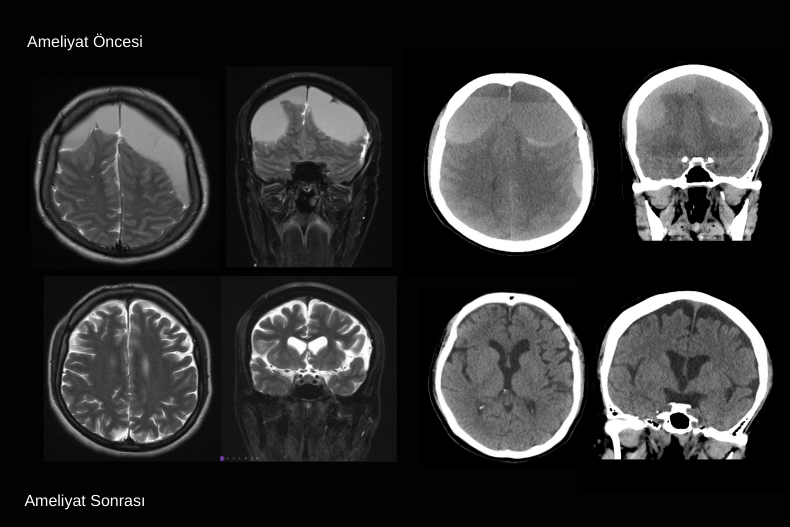

Malign MCA enfarktı çoğu zaman tek başına geniş bir beyin yarım küresini etkilerken, bazı olgularda tabloya ICA (Internal Carotid Artery) oklüzyonu da eşlik edebilir. ICA tıkanıklığında hem MCA hem de anterior serebral arter (ACA) sulama alanları etkilenebilir ve ortaya çıkan enfarkt alanı çok daha geniş olur. Bu durum BT’de yaygın hipodens alan, belirgin beyin ödemi, ciddi orta hat kayması (shift), ventrikül basısı ve bazal sisternlerin silinmesi ile kendini gösterir. Klinik olarak hızla bilinç bozulması gelişir ve beyin sapı herniasyonu riski artar.

Medikal tedaviye rağmen kötüleşen bu hastalarda uygulanan dekompresif kraniektomi, artmış kafa içi basıncını azaltarak hayatta kalma şansını artırır. Özellikle erken dönemde yapılan cerrahi, genç ve önceden bağımsız hastalarda mortaliteyi belirgin şekilde düşürür. Ancak ICA düzeyindeki geniş enfarktlar daha büyük beyin dokusu kaybına yol açtığı için fonksiyonel prognoz MCA’ya göre daha ağır olabilir. Buna rağmen uygun hasta seçimi ve zamanında cerrahi müdahale, yaşam kurtarıcı bir seçenek olarak önemini korur.